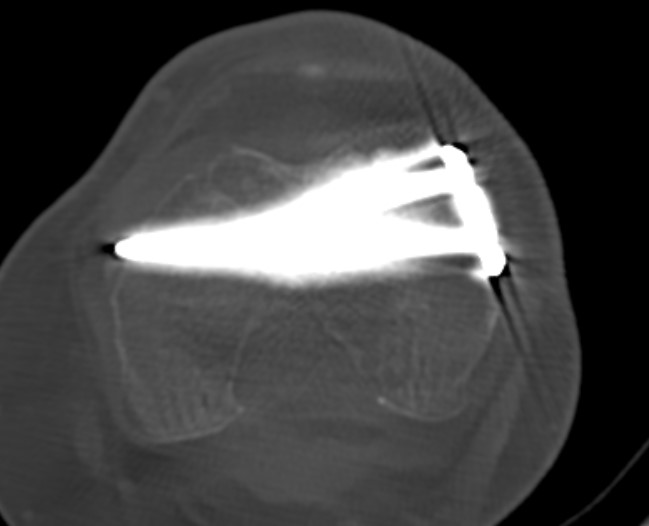

Type C: Complete articular

Xray / CT

Options

Dual Plate

Plate + Retrograde nail

Significant comminution

Loss of medial cortical buttress